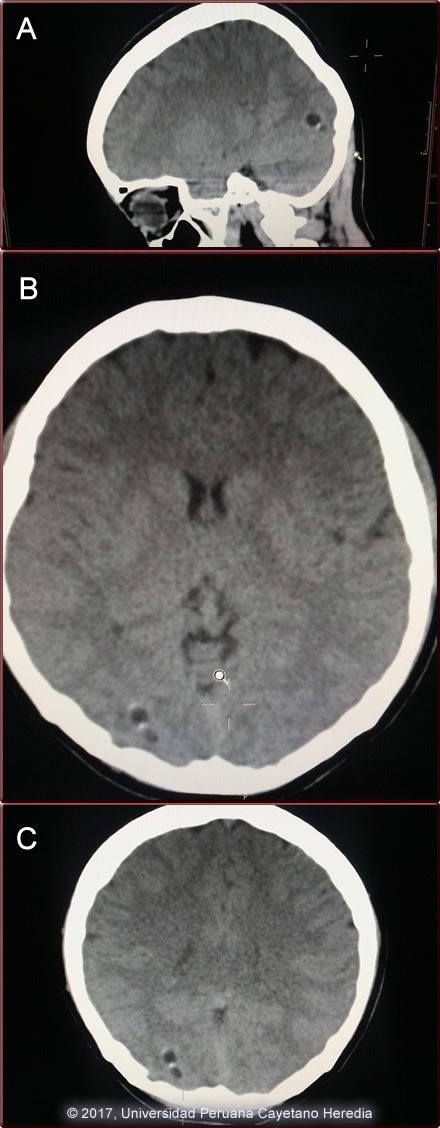

Epidemiology: Born and lived all her life in Cusco city in the Andean highlands. No illness in the family. No known TB contacts. Physical Examination: Blood pressure 120/70 pulse 89, afebrile. She was alert, oriented in no acute distress. Pupils equal and reactive, fundi clear. Physical examination and a detailed neurologic examination were normal. Laboratory: Hb 16.0 Hct 48.4 WBC 10.0 (normal differential, no eos) platelets 207 Glucose 96; Urea 21; Cr 0.67; normal liver enzymes. Normal Chest x-ray. Non-contrast head CT is shown (Images A,B,C).

![]() Discussion:Diagnosis of neurocysticercosis can be problematic, especially in patients with one or 2 lesions. The imaging studies usually show cystic lesions (as in this case), but often do not demonstrate the scolex, which can be diagnostic. Studies in southern India of patients with single enhancing lesions were used to develop a clinical definition of cysticercosis. They found that, in patients with seizures, the combination of a single round lesion less than 2 cm in diameter with no midline shift, no symptoms or signs of other diseases, and a non-focal neurologic examination was highly predictive of neurocysticercosis. In a prospective study, this definition had a sensitivity of 99% and a specificity of 98.9% for cysticercosis [Rajshekhar V et al. Acta Neurol Scand 1987;96:76]. This definition has been incorporated into current guidelines for diagnosis [Del Brutto OH et. al. J Neurol SCi 2017;372:202]. Our patient had 2 lesions rather than 1, but they were clustered together and essentially met those criteria. The non-contrast CT scans are shown. Image A is s sagittal view that shows two cysts close to each other in the right occipital area without obvious edema. Image C is a coronal view that shows the two cysts lesions. While there is no definite scolex, the focal area of increased density on the edge of the cystic area suggests a scolex. The scolex is the head of the larval T. solium tapeworm. Typical viable lesions with scolex are shown in image D (from another patient). Cysticercosis is infection with the larval stages of the human pork tapeworm Taenia solium. Humans acquire cysticercosis after ingesting eggs of T. solium in material contaminated with feces originating in human tapeworm carriers. Humans that do not eat pork can get cysticercosis. Ingestion of contaminated pork results in humans getting an adult intestinal tapeworm – not cysticercosis. Cysticercosis is common in many developing countries and very common in rural agricultural areas of Perú. In developed countries, the long-lived cysticerci are increasingly seen as immigration from affected areas rises. Occasional transmission by tapeworm carriers to those who have never left non-endemic countries is reported. Ingested T. solium eggs hatch in the stomach and are then carried to the muscles and other tissues where the larvae encyst and reach their usual size of about 1 cm within a few months. Separate clinical, diagnostic, and therapeutic considerations apply to patients with the 4 forms of neurocysticercosis: intraparenchymal, ventricular, sub-arachnoid or spinal. See Gorgas Cases 2014-10, 2011-06, 2007-02, and 2006-04 for discussion of these presentations. The cysticerci seem able to evade the immune system and are thought to remain viable for several years without causing any inflammatory response, so that most infected patients are asymptomatic for years alter infection. Most clinical symptoms are the direct result of inflammatory responses that accompany the eventual cyst degeneration, but most patients likely remain asymptomatic even as cysts die. Epileptic seizures are the primary or sole clinical manifestation in up to 80% of symptomatic patients. In endemic regions new onset seizures in teenagers or young adults is most likely due to neurocysticercosis. Cysticerci can also cause symptoms because of mass effect, impingement on a vital structure or, especially if the cyst is intraventricular, blockage of CSF circulation. Patients with one or 2 parenchymal cysticerci have a relatively benign form of the disease. Even without specific treatment, the disease is usually self-limited. Based on that some clinicians had recommended not using antiparasitic treatment. However, the time course is often prolonged. Two meta-analyses of randomized trials have been published on treatment of patients meeting the definition of solitary cysticercal granulomas [Zhao BC et al. PLoS Neg Trop Dis 2016;10(2):e0004418; Otte WM et al. Neurology 2013;80:152] . Overall, the radiographic resolution is more rapid and the number of seizures during the 6 months after diagnosis is improved in patients treated with a short course of albendazole and corticosteroids (typically 1-2 weeks). However, that treatment did not decrease the proportion of patients who subsequently developed calcifications on CT scan and did not impact the frequency of seizure more than 6 months after presentation. Interestingly, most patients with a single lesion resolve without forming calcifications. In those with few seizures and radiographic resolution (which usually occurs within 6 months of albendazole treatment), anti-epileptic drugs can safely be tapered off. Parenchymal neurocysticercosis with more than 2 viable and/or degenerating cysts should be treated with Albendazole 15 mg/kg per day (max. 800 mg/day) + Praziquantel 50 mg/kg per day + Dexamethasone 0.1 mg/kg/day beginning 1 day prior to anti parasitic drugs] x 10 days ± Anti-seizure medication if needed [Garcia HH et. al. Lancet Infect Dis 2014;14:687]. Some data suggest that higher doses of corticosteroids may decrease early seizures. Albendazole alone without praziquantel is likely adequate if only 1-2 cysts on an MRI. Dead, calcified cysts only require no antiparasitic treatment. Our patient responded rapidly to albendazole and steroids. |